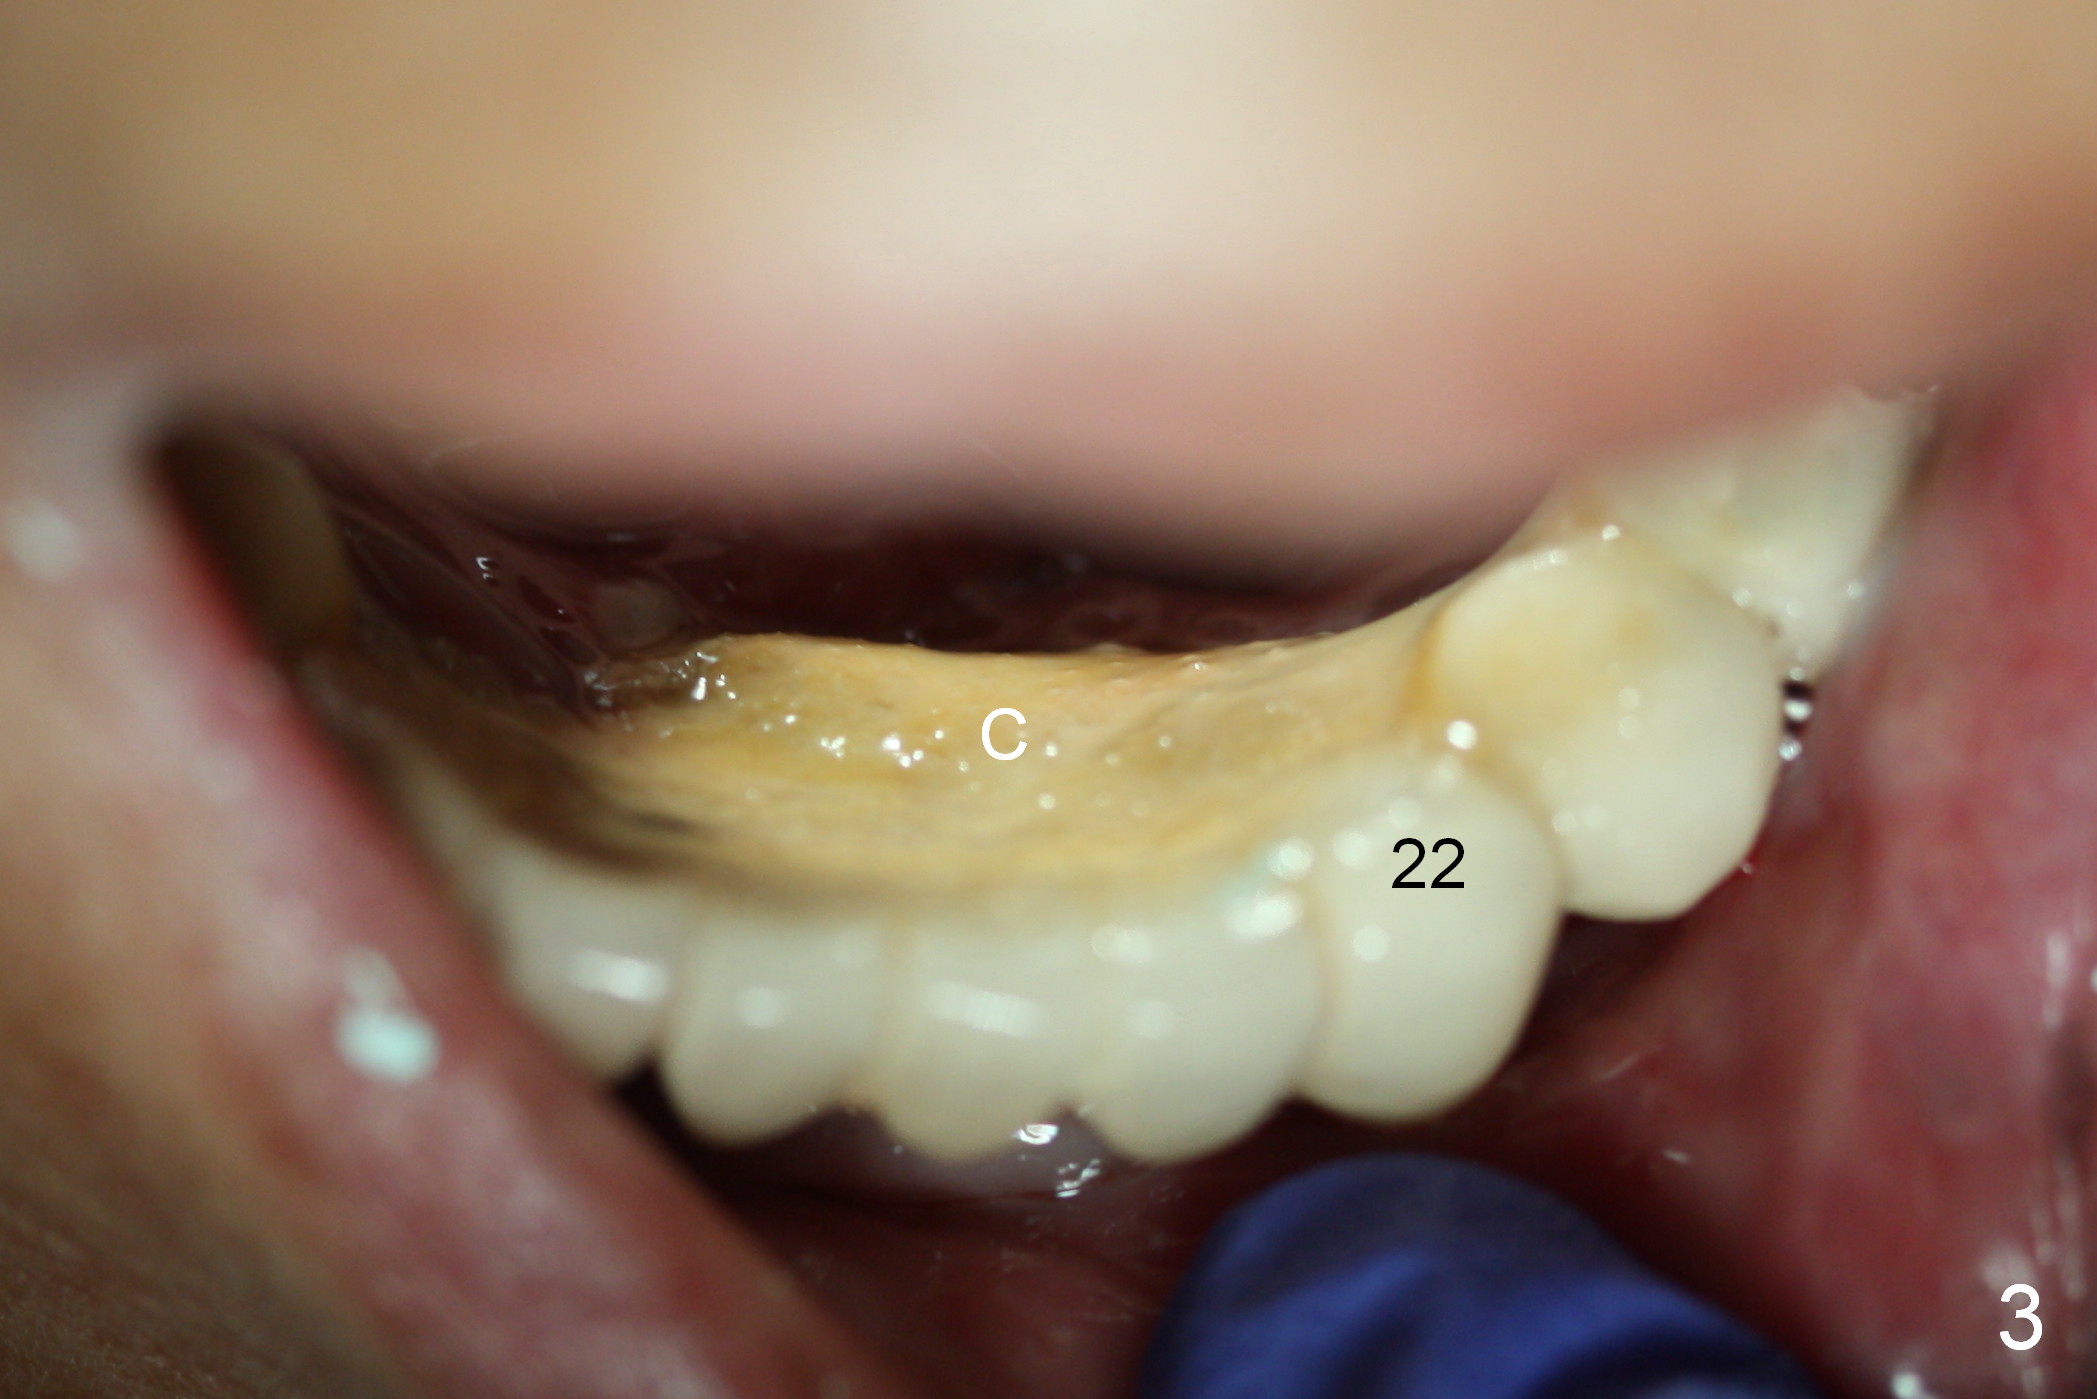

A 72-year-old woman has severe pain associated with one of three abutments of a long-spanned bridge (Fig.1,2: #22). The lingual calculus is extremely large (Fig.3 C). When the bridge is sectioned between #26 and 27, the tooth #22 is easily separated from the socket (Fig.4). In fact, the large supragingival calculus causes hemorrhagic indentation in the lingual vestibule (Fig.5,6: I). Due to finance, socket preservation is done at #22 with 6-month collagen membrane buccally and .5-1.5 mm allograft and collagen plug (Fig.6 *).